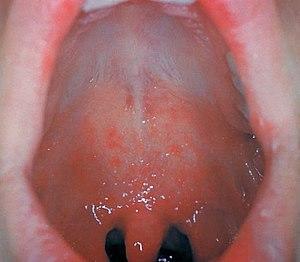

Rubella (German measles) enanthema

Enanthem or enanthema is a rash (small spots) on the mucous membranes.[1] It is characteristic of patients with viral infections[2] causing hand foot and mouth disease, measles, and sometimes chicken pox, or COVID-19.[3] In addition, bacterial infections such as Scarlet fever may also be a cause of enanthema. The aforementioned diseases usually present with exanthema and enanthema.

Enanthema can also indicate hypersensitivity.[4]